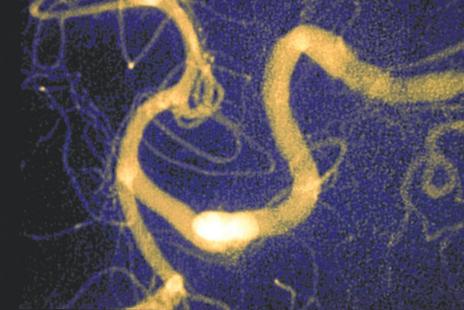

Accident vasculaire cerebral

avc neurologie hemoragie

Accident vasculaire cerebral avc neurologie hemoragie

Crédit photo : Phanie